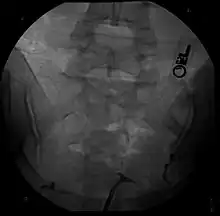

Class VIDES uterus.

Hysterosalpingography of a T shaped uterus

The uterine cavity has a "T-shape" as a result of fetal exposure to diethylstilbestrol.